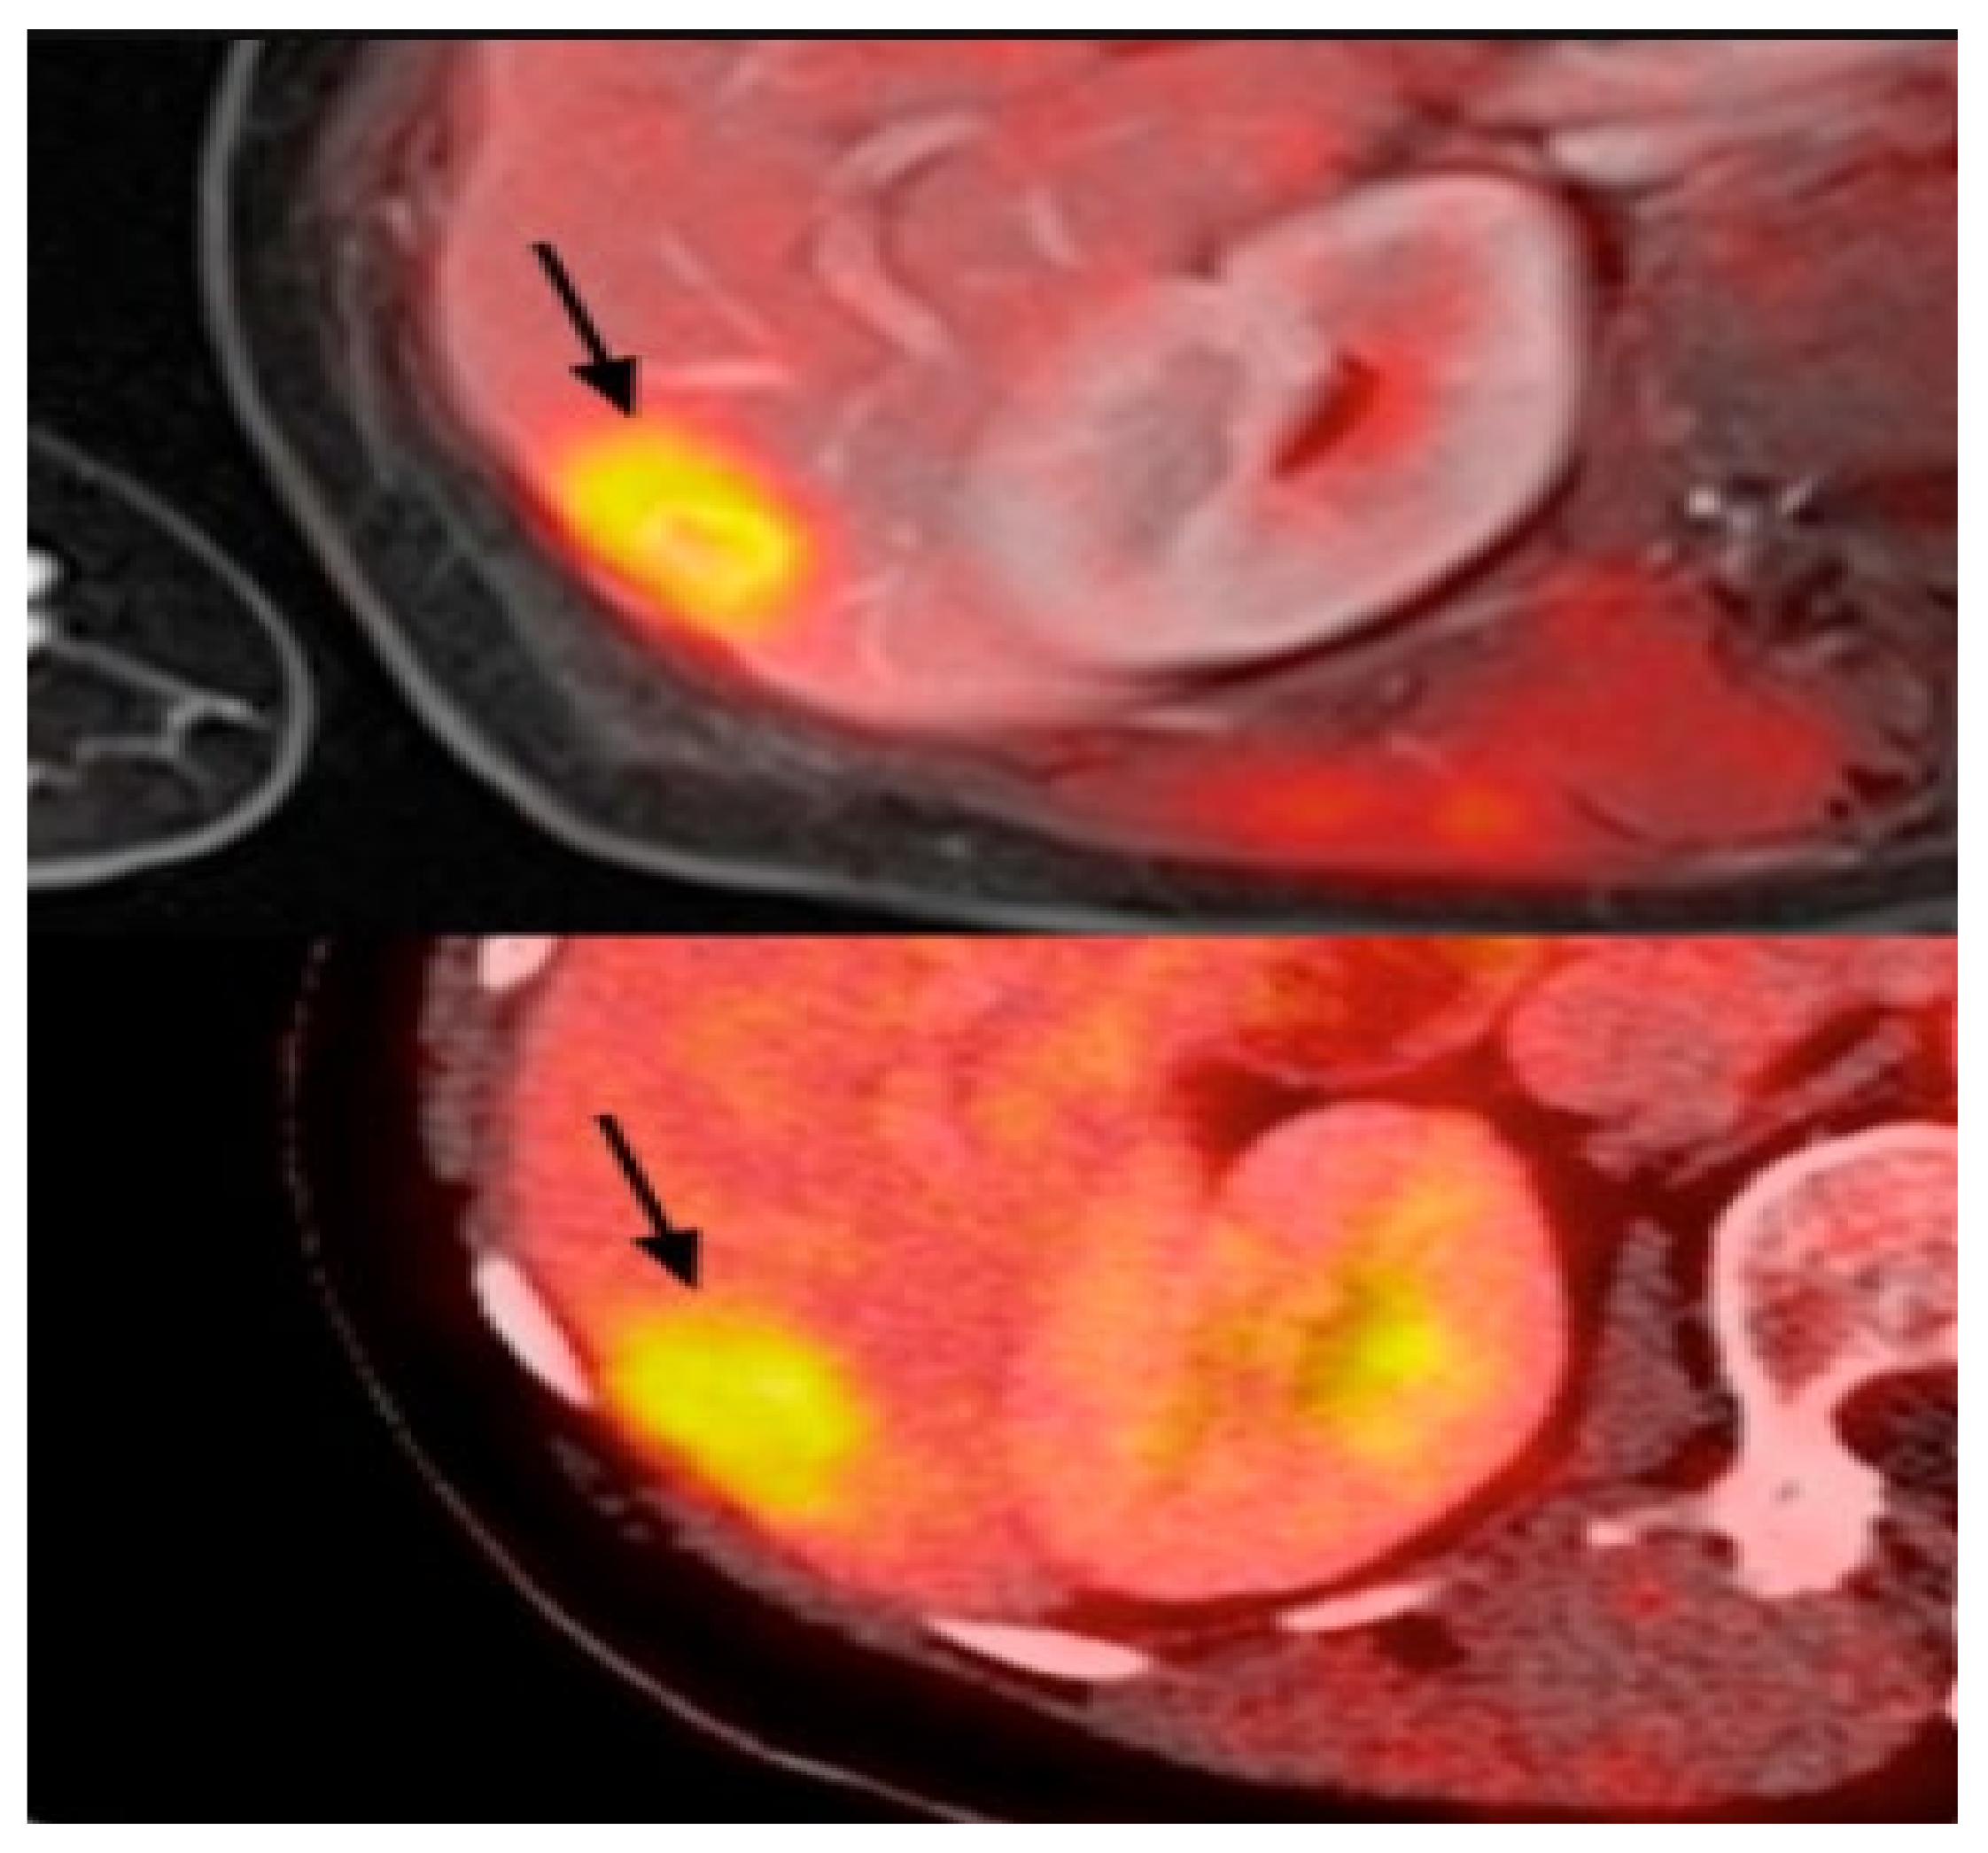

2.6. Positron Emission Tomography (PET)

3.2.5. Positron Emission Tomography (PET)/Computed Tomography (CT)